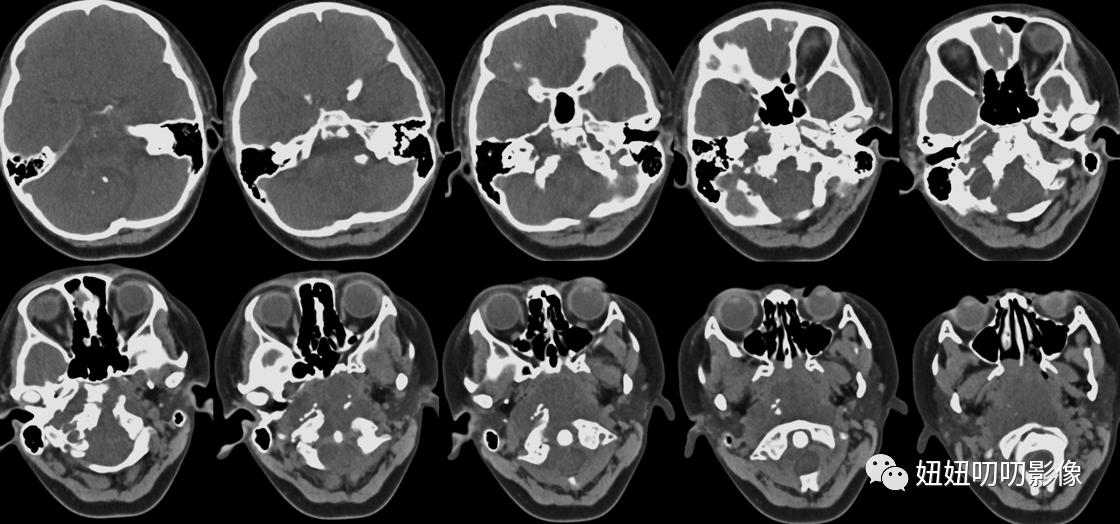

CT:鼻咽、口咽部后壁见一低密度软组织肿块,CT值约29Hu,边界不清,大小约5.8x4.6x6.1cm,内见斑片状高密度灶,包绕枕骨斜坡及右侧岩锥、右侧枕骨,骨质不同程度破坏。双侧咽隐窝、显示不清,病灶向鼻咽、口咽腔内凸出。双侧上颌窦、筛窦、蝶窦、额窦气化良好,窦腔显示清晰,未见明显粘膜增厚。

CT:鼻咽、口咽后壁巨大软组织肿块,枕骨斜坡、右侧岩锥、右侧枕骨骨质破坏;符合恶性肿瘤CT表现。建议MR检查。